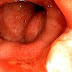

Proctitis is an inflammation of the anus and the lining of the rectum, affecting only the last 6 inches of the rectum.

Doctors can diagnose proctitis by looking inside the rectum with a proctoscope or a sigmoidoscope. A biopsy is taken, in which the doctor scrapes a tiny piece of tissue from the rectum, and this tissue is then examined by microscopy. The physician may also take a stool sample to test for infections or bacteria. If the physician suspects that the patient has Crohn's disease or ulcerative colitis, colonoscopy or barium enema X-rays are used to examine areas of the intestine.